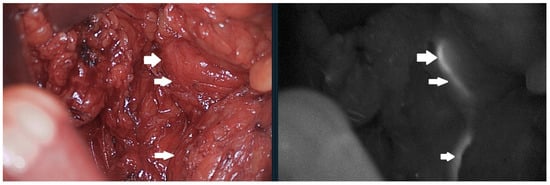

4.1. Fluorescent Visualisation of The Ureters

4.2. Tissue Perfusion for Anastomotic Creation

4.3. Colorectal Multichannel Visualisation